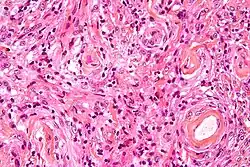

Histopathology of a typical WHO grade 1 meningioma, H&E stain. It is of the meningothelial histologic type, which is the most common meningioma type. It shows its typical findings:

- A woven architectural pattern

- Psammoma bodies (spheroid calcifications)

- Syncytial cells (having indistinct cell membranes) with eosinophilic (pink) cytoplasms

- Round uniform nuclei

- Whorls (concentric cell arrangements)[16]

Micrograph of a meningioma showing the characteristic whorling, HPS stain

Histologically, meningioma cells are relatively uniform, with a tendency to encircle one another, forming whorls and psammoma bodies (laminated calcific concretions).[19] As such, they also have a tendency to calcify and are highly vascularized.